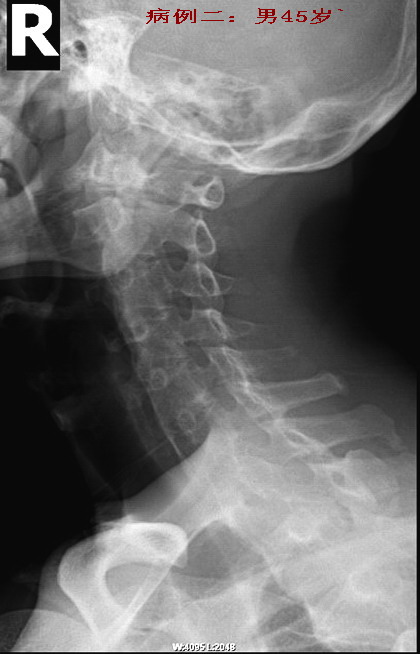

病例二:强直性脊椎炎晚期病例。

男性45岁,患者已有明显的颈部强直症状。从骶髂关节上行至颈椎均呈典型改变(腰椎侧位片已遗失.没有也无所谓)。